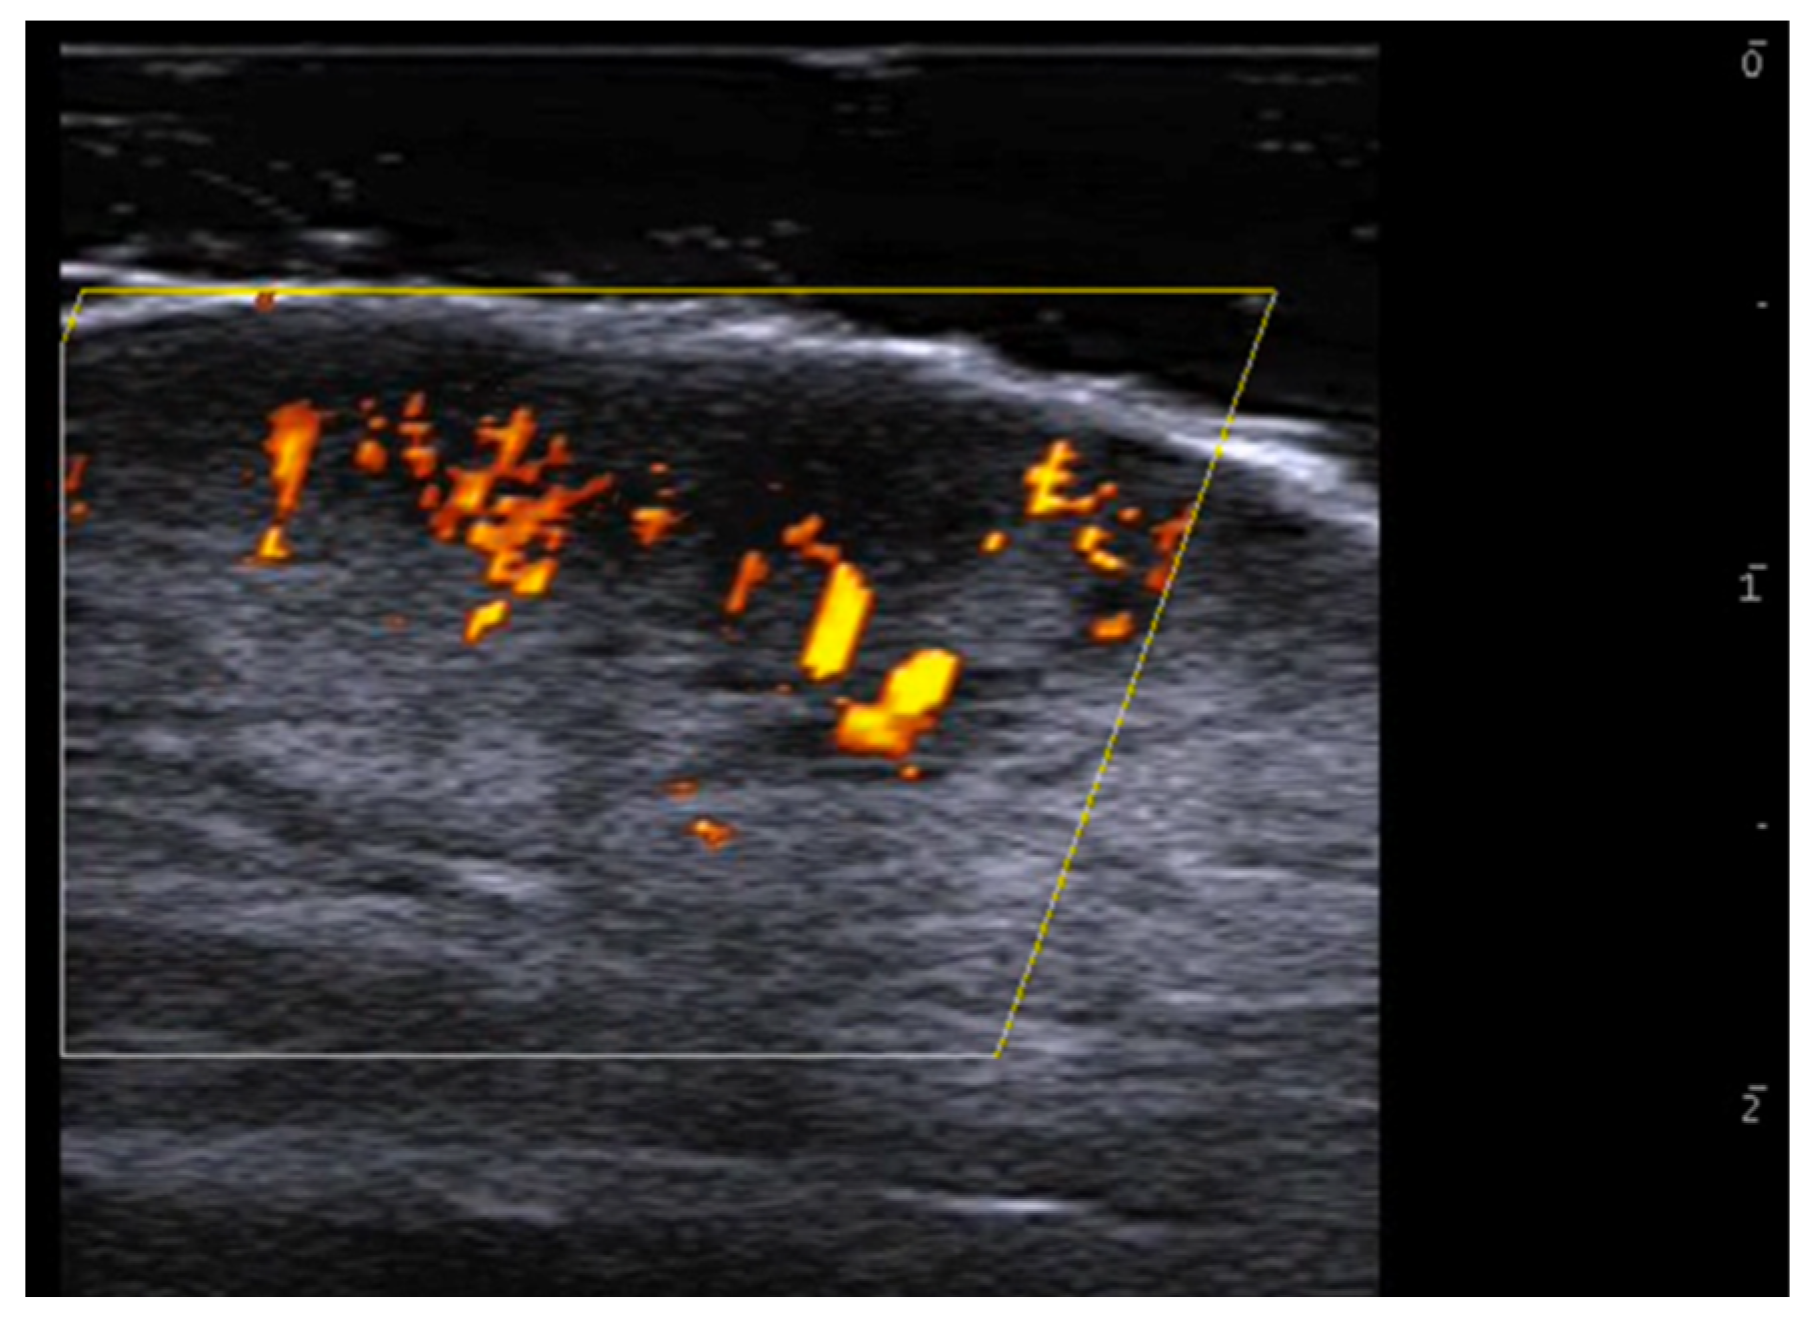

- Parra-Cares, J.; Wortsman, X.; Alfaro-Sepúlveda, D.; Mellado-Francisco, G.; Ramírez-Cornejo, C.; Vera-Kellet, C. Color Doppler Ultrasound Assessment of Subclinical Activity with Scoring of Morphea. J. Cutan. Med. Surg. 2023, 27, 454–460. [Google Scholar] [CrossRef] [PubMed]

- Wortsman, X.; Vera-Kellet, C. Ultrasound Morphea Activity Scoring (US-MAS): Modified US-MAS. J. Ultrasound Med. 2023, 42, 2447–2450. [Google Scholar] [CrossRef] [PubMed]